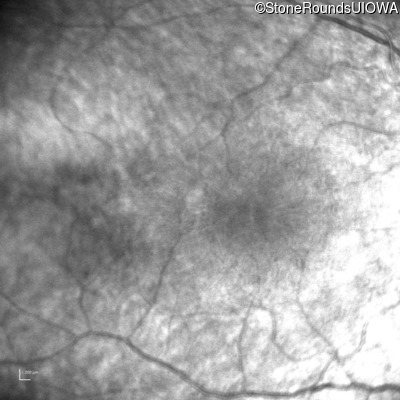

Infrared Fundus Photograph - Right - No Light Perception

Exemplar